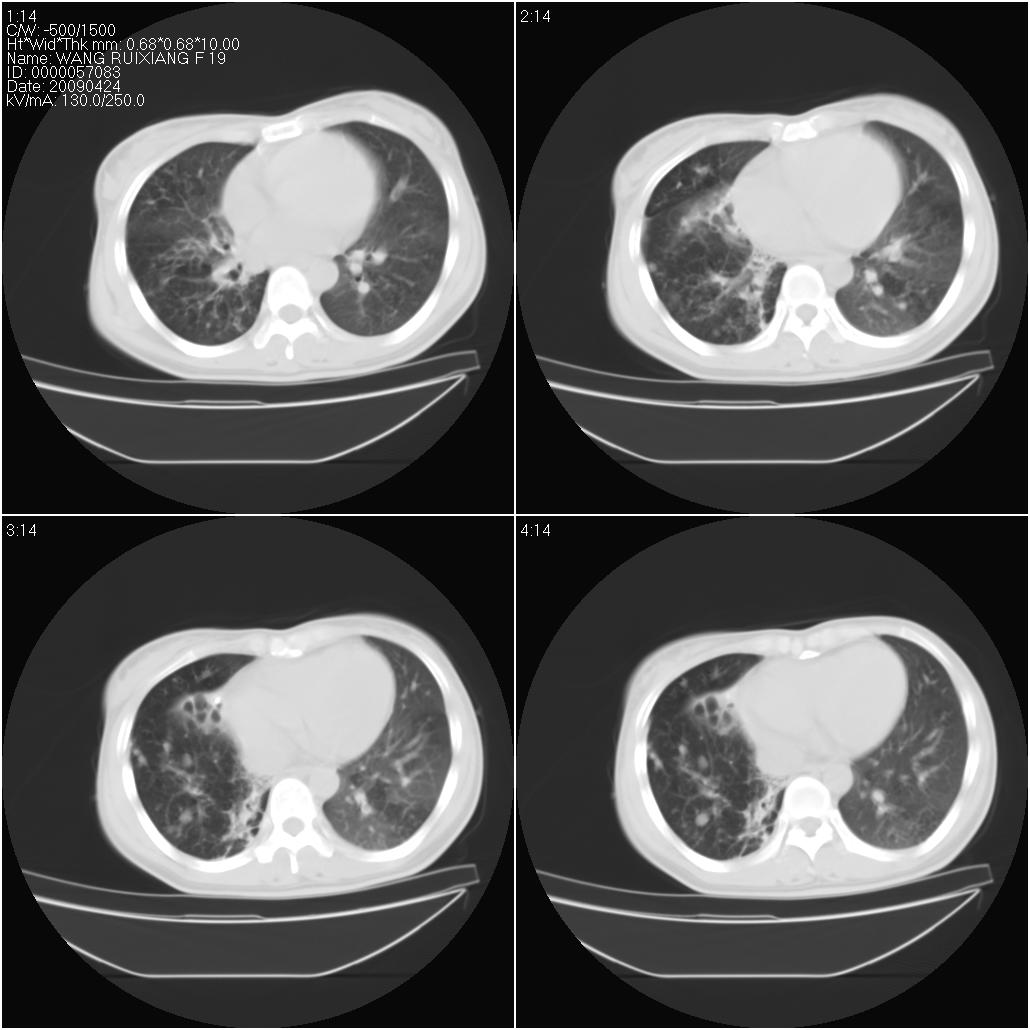

标题: CT19588:女性,39岁。患者胸闷不适,上楼时气喘。 [打印本页]

标题: CT19588:女性,39岁。患者胸闷不适,上楼时气喘。

片子上的年龄为19岁,是操作错误。该患者于去年5月份曾做平片和ct扫描,和这一次的ct检查没有明显变化。当时诊断为肺结核,进行抗痨治疗至今,但没有改善。呼吸功能试验为混合型呼吸困难。除此之外,该患者没有其他方面没有的临床症状和体征

考虑肺淋巴管腺肌病,其次考虑间质性肺炎\\肺间质纤维化及韦格氏肉芽肿等

两肺见斑点片状阴影,部分病灶密度较高,右下肺见小囊状及柱状蜂窝状阴形,考虑为两肺结核以阵旧性为主,右下肺支扩。

考虑肺淋巴管肌瘤病。

结合病人年龄(特别是生育期妇女)及临床表现多考虑淋巴管肌瘤病。